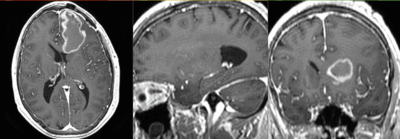

this is the fixed T1 reference image. All images are aligned into this space this is the FLAIR scan, to be registered with the T1 lleft this is the T1Gd image, serves as reference to which all others are aligned lleft this is the DTI tensor image, to be registered with the T1

moving image 2a

T1Gd

• moving : T1Gd axial

• however the FLAIR is low resolution. The T1 is very high in-plane resolution, which causes memory issues when trying to resample the DTI to that resolution. So we choose the T1Gd as the reference space and resolution (1x1x1 mm).

DTI aligned with T1Gd DTI aligned with T1Gd

DTI deformation applied (before/after registration DTI deformation applied (before/after registration